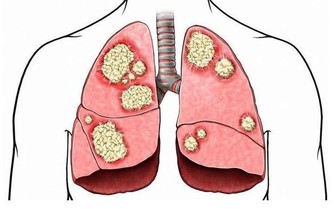

比如異煙肼、利福平等抗結核藥,

再比如多數的抗腫瘤藥。西藥因藥物結構明確,相比中藥,肝損傷較為明確!